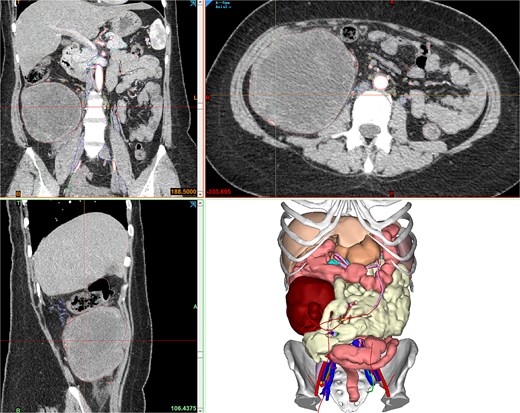

Contrast-enhanced abdominopelvic computed tomography (CT) (20 August 2024) identified a heterogeneous, hypodense mass (12 × 10.5 × 8.5 cm) arising from the ileocecal region, partially encasing the appendiceal base and colonic wall. Pelvic magnetic resonance imaging (MRI) further delineated the mass’s origin from the terminal ileum, showing adherence to the ileocolic vasculature without invasion of adjacent organs (Fig. 1). To refine surgical planning, a patient-specific 3D-printed model was generated using Mimics23 software (Materialize NV), which highlighted critical anatomical relationships, including compression of the ileocolic artery and proximity to the right ureter (Fig. 2).

Contrast-enhanced CT showing the retroperitoneal mass, and Mimics23 3D model (tumor: red; ileum; vasculature; 3-Matic®15).

Mimics23 3D model (3-Matic®15 simulation of surgical margins). Blue arrow: ileocecal region; yellow arrow: appendix.